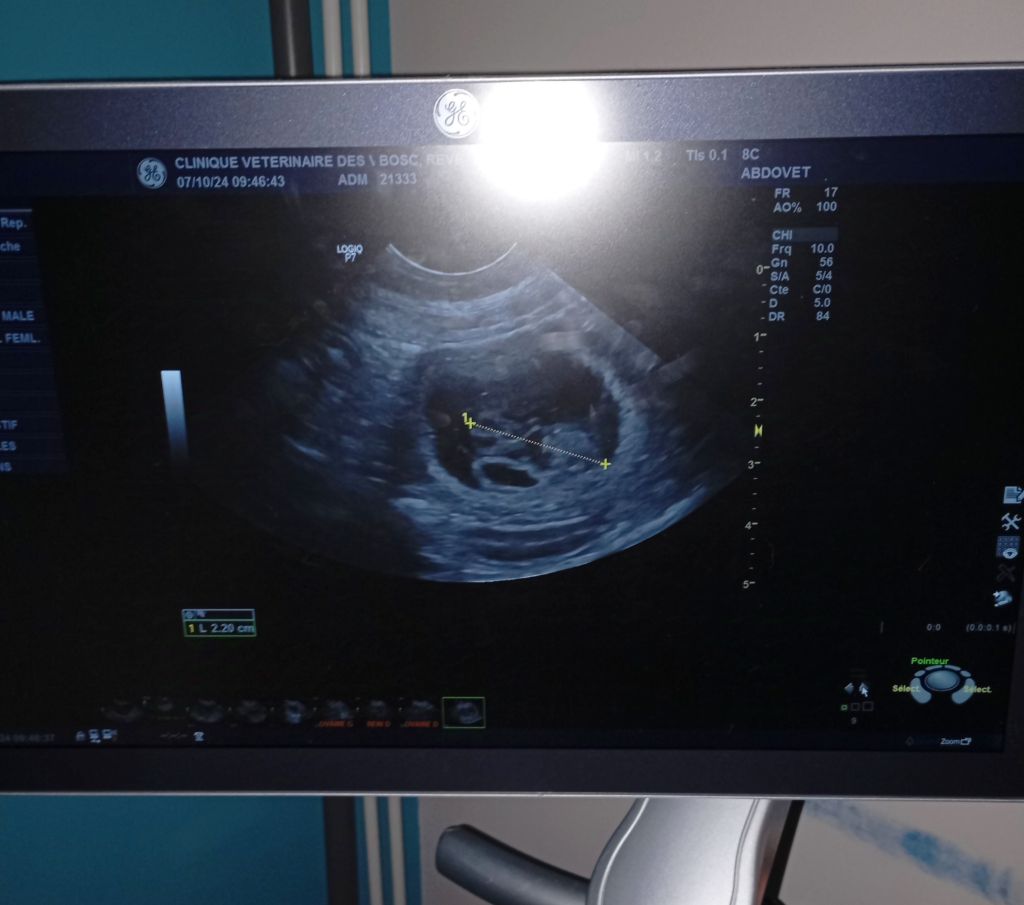

Notre Rêve et notre Saicko vont bientôt avoir des bébés, courant novembre 2024....